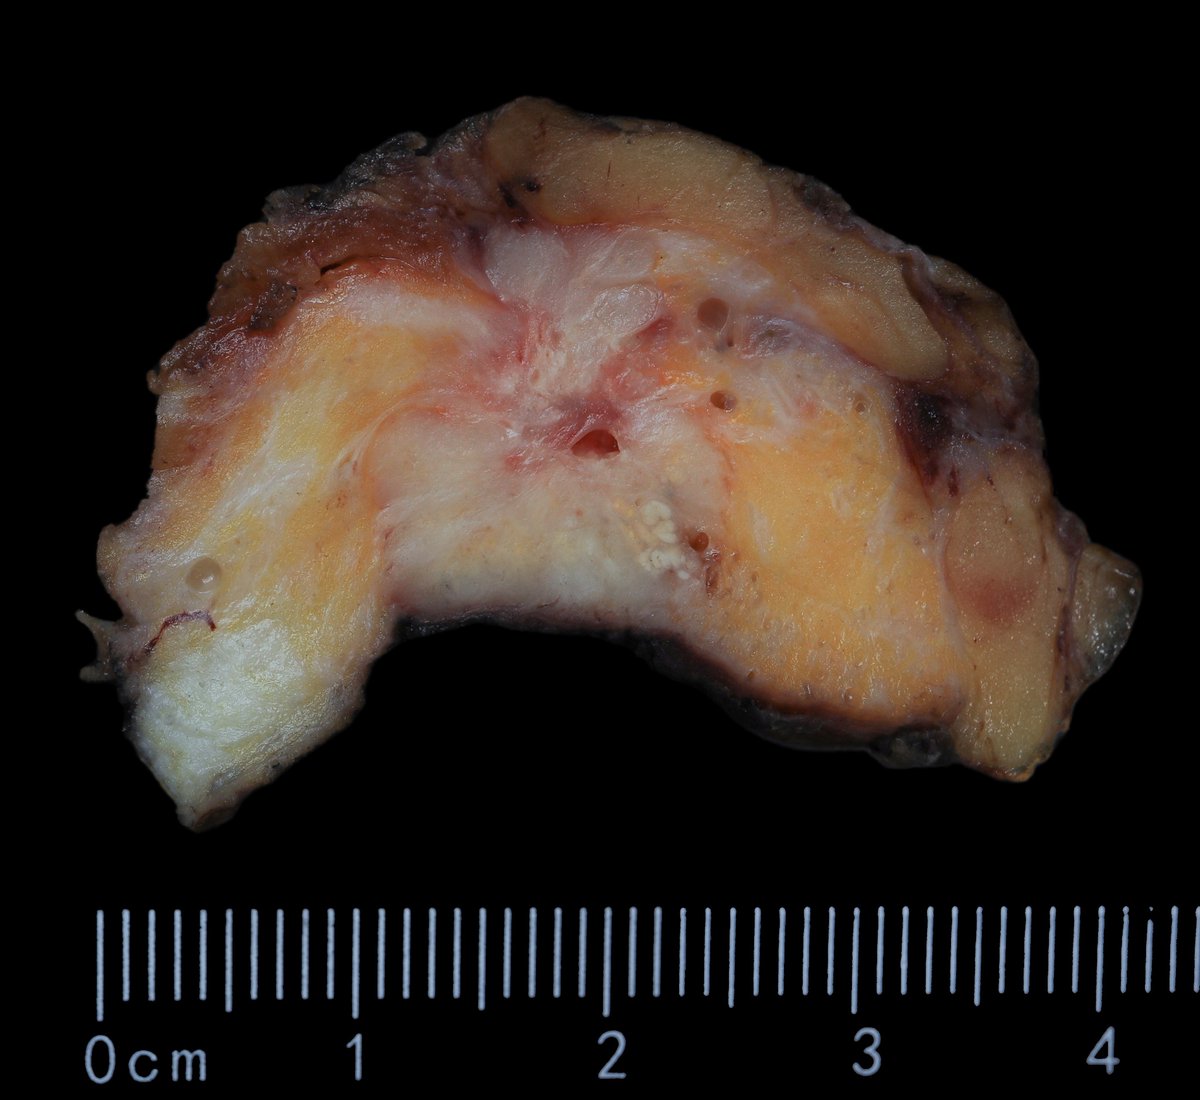

F40y,chronic cavitary pulmonary aspergillosis, atypical resection of the low lobe of the lung.

several cavities with a fungal ball, granulation tissue, chronic inflamation, metaplastic squamous epithelium, calcium oxalate crystals